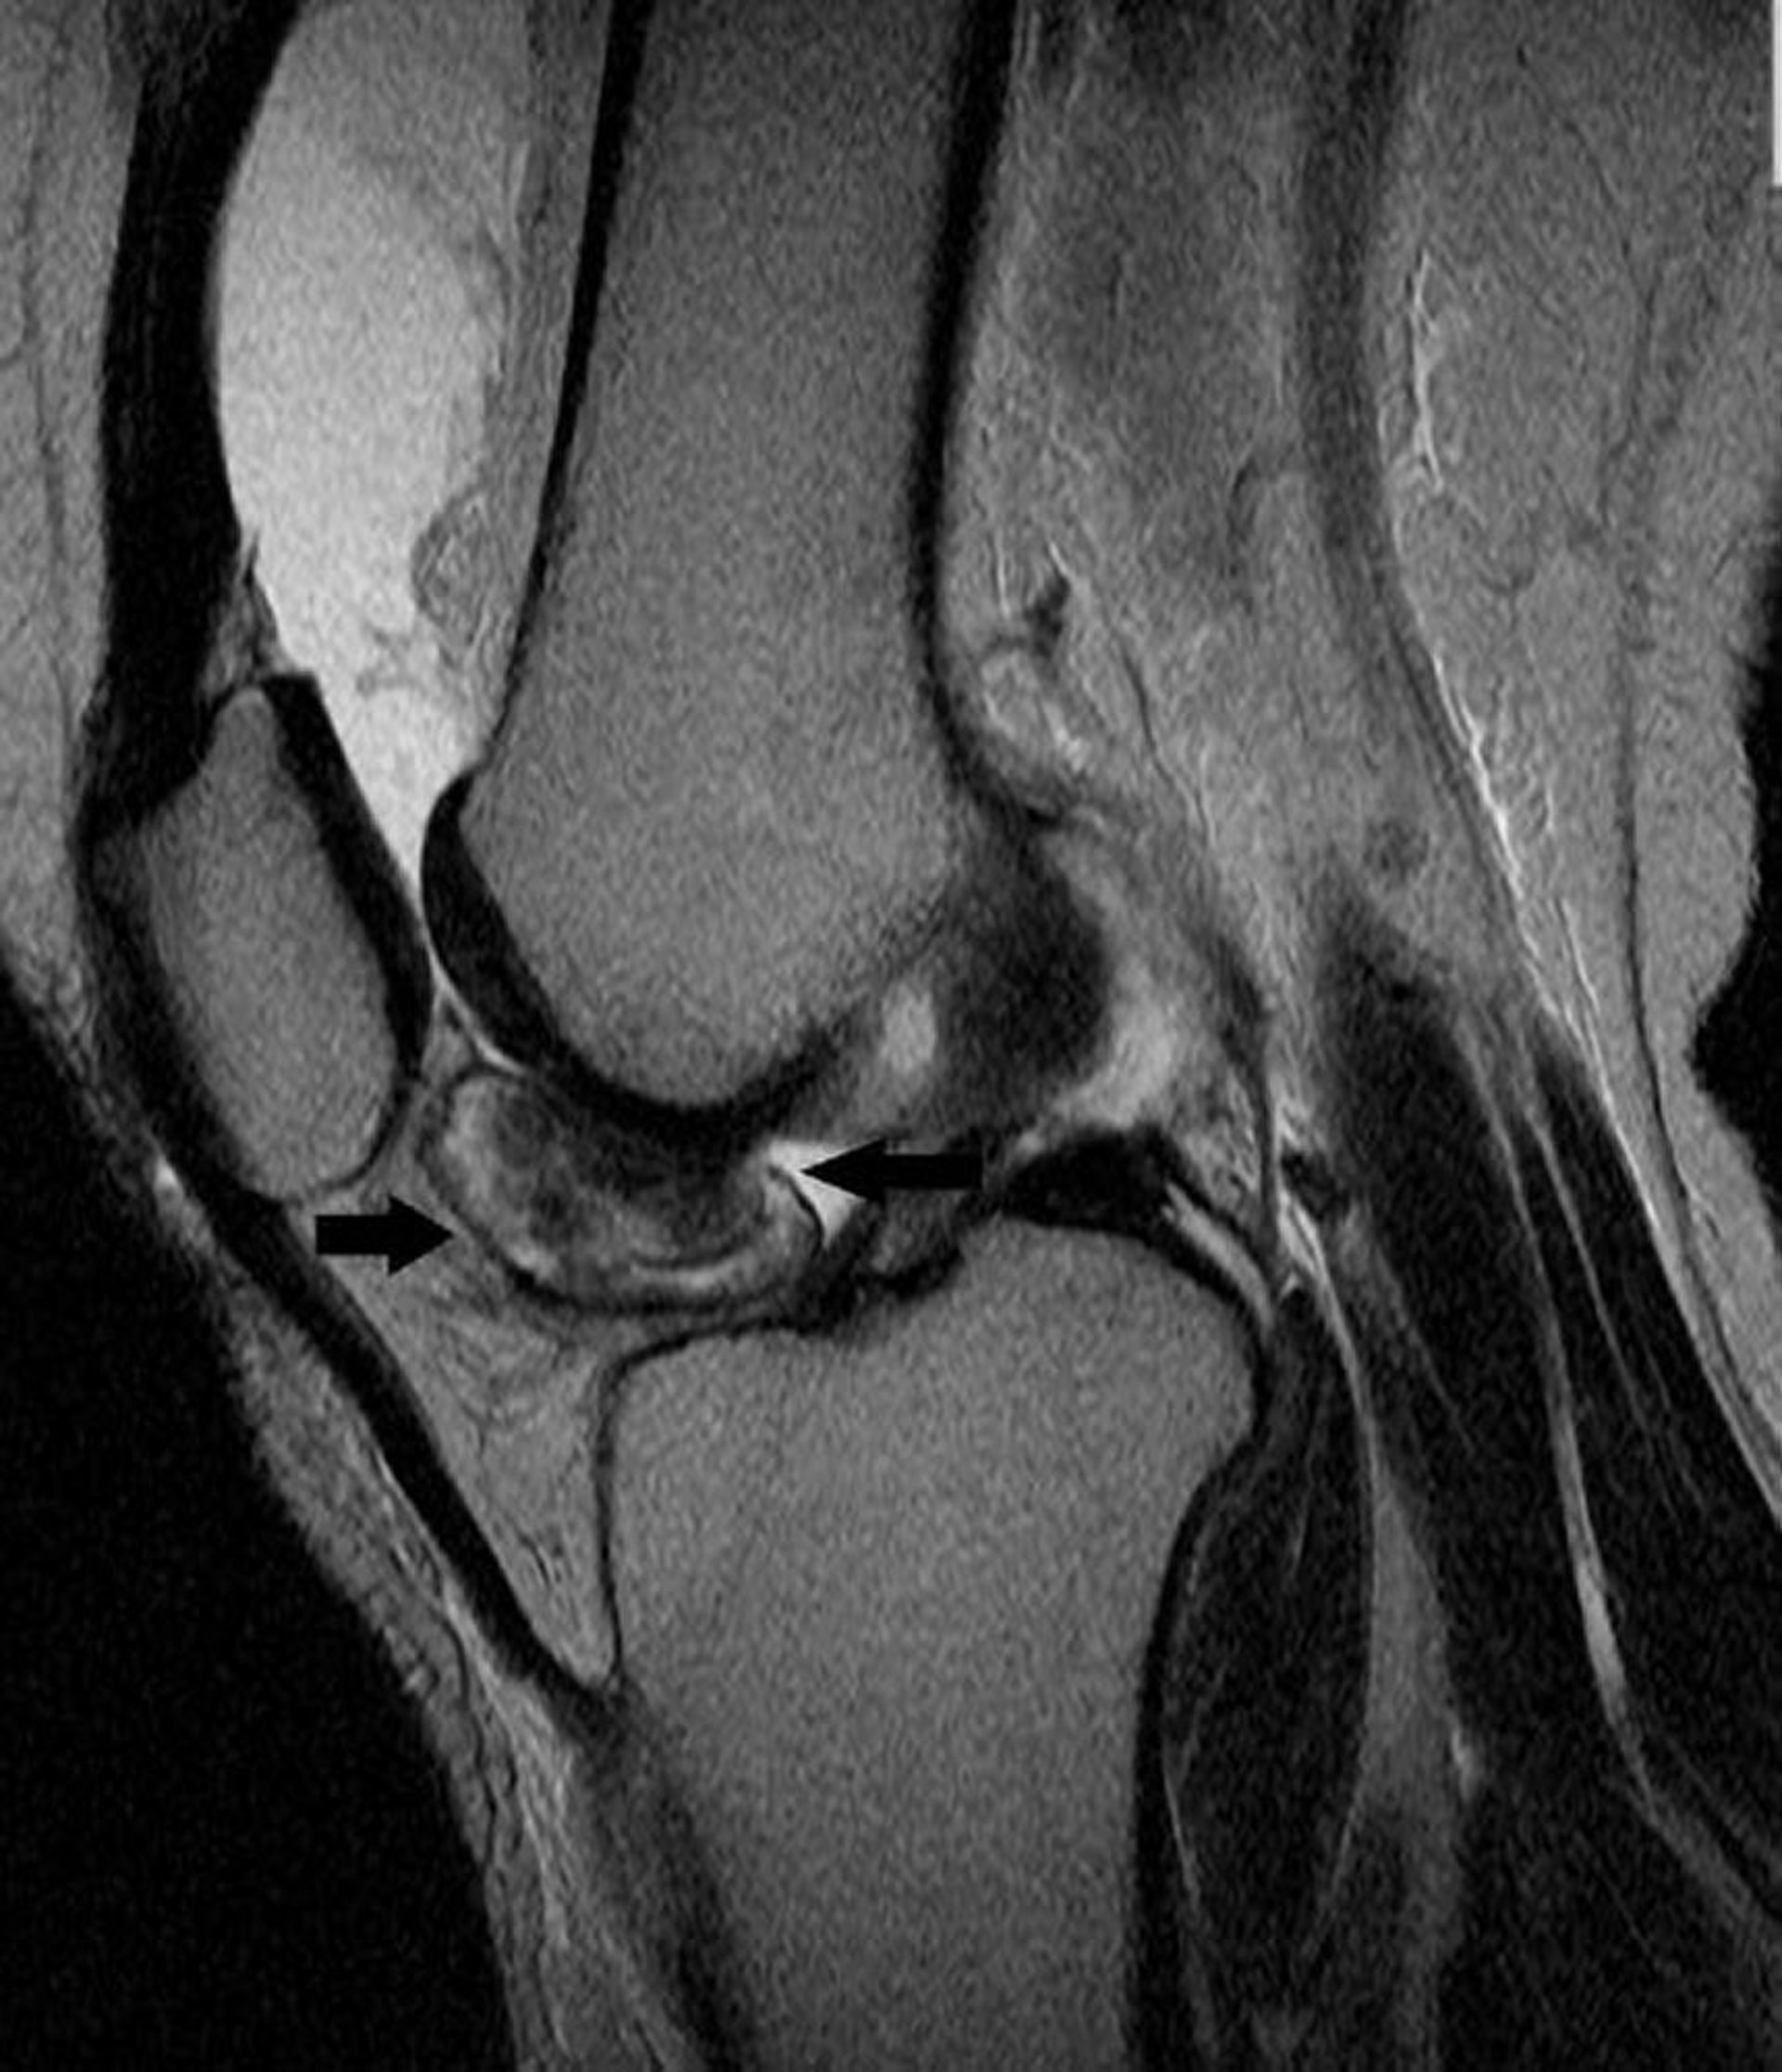

Теносиновиальная гигантоклеточная опухоль

Данный снимок МРТ коленного сустава демонстрирует теносиновиальную гигантоклеточную опухоль в синовиальной оболочке коленного сустава (стрелки).

Image courtesy of Michael J. Joyce, MD, and Hakan Ilaslan, MD.